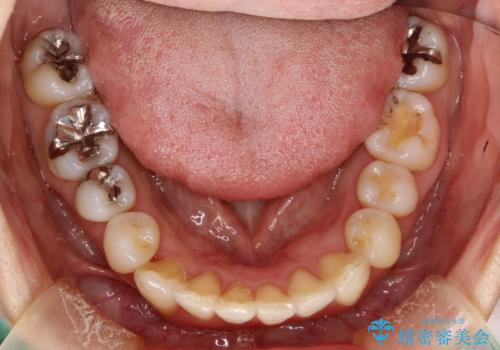

- 上下のがたつきを主訴に来院された患者様です。

上下の前歯と奥歯にがたつきがありました。

上下の奥歯を後方に移動させるのと、歯と歯の間をわずかに削ることでスペースを作り、歯を並べる計画としました。